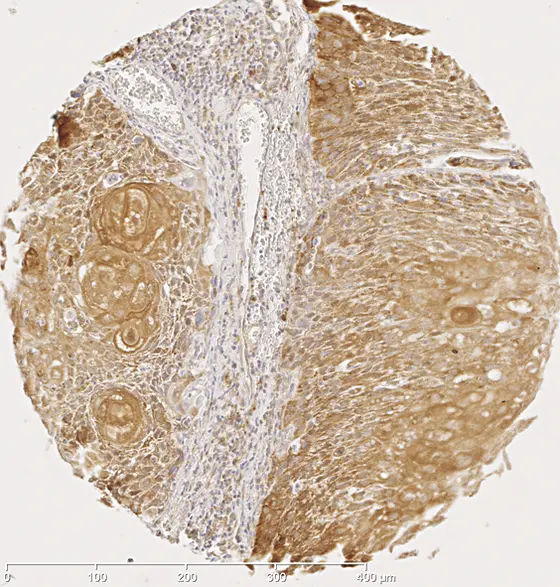

Bei Krebserkrankungen des Mund-Rachenraumes handelt es sich meist um so genannte Plattenepithelkarzinome, die aus Zellen der Schleimhäute entstehen. Bekannte Risikofaktoren für diese Erkrankung sind Alkohol und Zigaretten. Jedoch steigen die Fallzahlen, auch bei Menschen, die weder trinken noch rauchen. „Bei diesen Patienten liegthäufig eine Infektion mit krebserregenden Typen der humane Papillomviren (HPV) vor“, sagt PD Dr. Jochen Hess, der im Deutschen Krebsforschungszentrum eine Nachwuchsgruppe und an der Universitäts-HNO-Klinik Heidelberg eine Forschergruppe leitet. „Insgesamt sind bis zu 60 Prozent aller Plattenepithelkarzinome im Mund-Rachenraum positiv für HPV16, den Erreger, der auch Krebs am Gebärmutterhals auslöst.“

Das Ergebnis wurde zunächst an 100 Tumorproben aus Heidelberg erzielt und im Anschluss daran an Tumorgewebe von insgesamt 120 weiteren Patienten aus Leipzig und Chicago bestätigt. Vier der fünf betroffenen Gene regulieren den Retinolsäure-Stoffwechsel, der sich auf das Wachstum, die Differenzierung und den Tod von Zellen auswirkt. Dass sich die epigenetischen Veränderungen auch tatsächlich auf die Biologie der Krebszellen auswirkten, wiesen die Forscher ebenfalls nach: Die Menge an RNA-Abschriften der fünf Gene entsprach dem, was die veränderte Methylierung des jeweiligen Gens erwarten ließ.